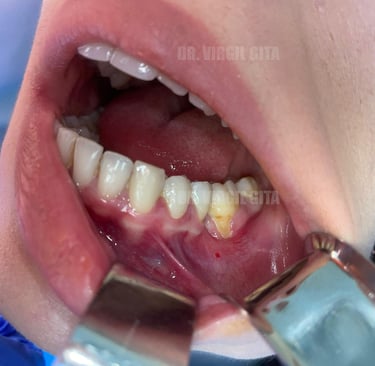

Tratament retractie gingivala post tratament ortodontic cu lambou tractionat coronar si grefa de tesut conjunctiv prelevata de la nivelul palatului + membrana PRF